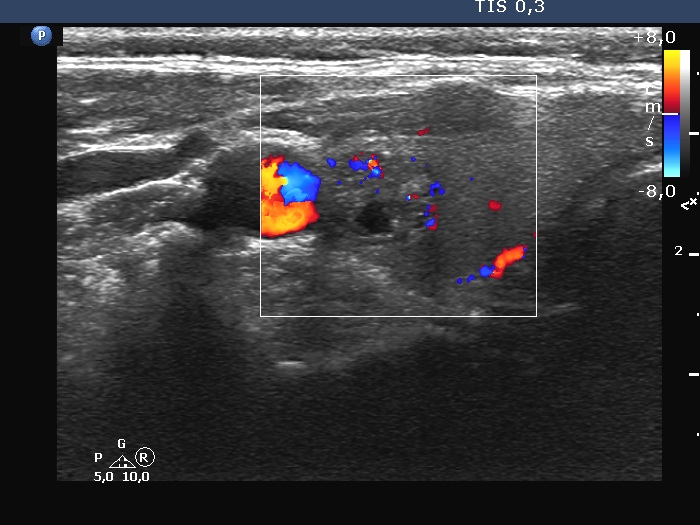

Ultrasonography. The thyroid was echonormal. There was a dominantly solid nodule in the right lobe. The lesion showed back wall cystic figures caused by posterior enhancement and nonparallel orientation. The depth of the nodule was 12 mm while the width was 10 mm.